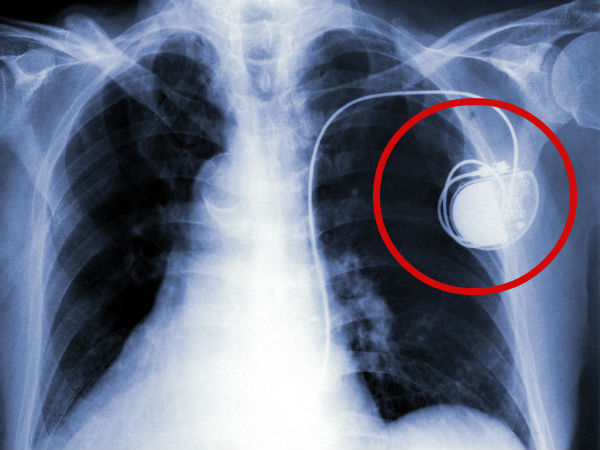

"பேஸ்மேக்கர்" பற்றி அனைவரும் கட்டாயம் தெரிந்துக்கொள்ள வேண்டிய விஷயங்கள்!!

இதயத்துடிப்பு குறைவாக இருப்பவர்கள் அல்லது இதயம் சீராக துடிக்கும் அளவிற்கு வலு குறைவாக இருப்பவர்களுக்கு பொதுவாக "பேஸ்மேக்கர்ஸ்" வைத்து, இதன் உதவியோடு இதயம் சீராக துடிக்க வைப்பார்கள். "பேஸ்மேக்கர்ஸ்" வைத்து இதயம் சீராக இயங்க ஆரம்பித்தாலும் கூட, "பேஸ்மேக்கர்ஸ்" வைத்தவர்கள் மற்றவர்கள் செய்யும் சில சாதாரண வேலைகளை செய்ய கூடாது, மற்றும் சில இடங்களுக்கு செல்ல கூடாது என்ற நிபந்தனைகள் இருக்கின்றன.

இந்த வகையில், "பேஸ்மேக்கர்ஸ்" பற்றி அனைவரும் கட்டாயம் தெரிந்துக்கொள்ள வேண்டிய விஷயங்கள் தான் நாம் இந்த கட்டுரையில் காணவிருக்கிறோம்...